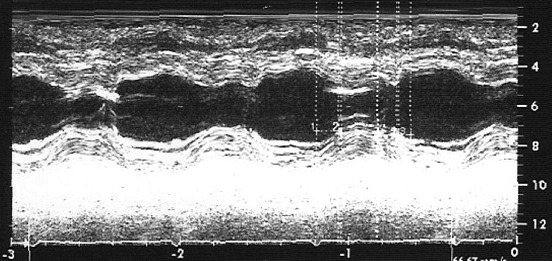

QT-nin uzanması sindromunda dinamik repolyarizasiya dəyişmələri nümunələri Dərc edilib: Cild 1, Nömrə 1, 2012 / Nəşr tarixi: 10.04.2012

Fərid Əliyev, Cengizhan Türkoğlu